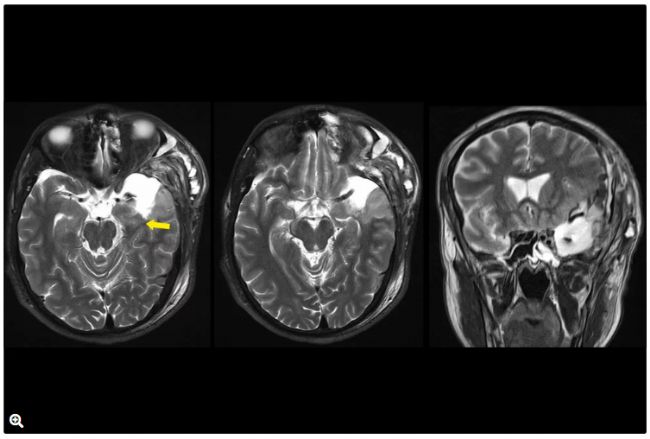

術前成像

圖1:T1加權腦MRI圖像,顯示AVM病灶位于左顳極并伴有靜脈動脈瘤(紅色箭頭)。

圖2:T2加權腦MRI圖像,顯示AVM病灶位于左顳極,伴有顯示血流典型流空。病變誘發(fā)左側海馬水腫(高信號,紅色箭頭)。

圖10:T2加權MRI圖像,顯示AVM切除后左側海馬正常信號(黃色箭頭)。